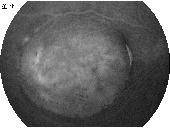

优秀眼底图片奖应征作品展示

17 18 19 20